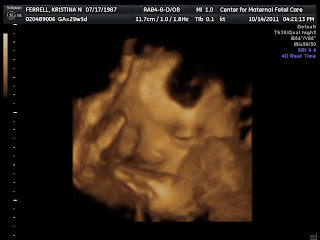

Some pictures from this week's ultrasound:

I just love the smirk in this one! :)

He's got my nose

Profile